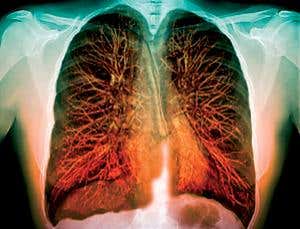

Breath easy (Image: Zephyr/SPL)

TASTE receptors for bitter flavours have been discovered in lung tissue. What’s more, they respond to bitter substances by dilating the airways of asthmatic mice, paving the way for a different approach to asthma treatment.